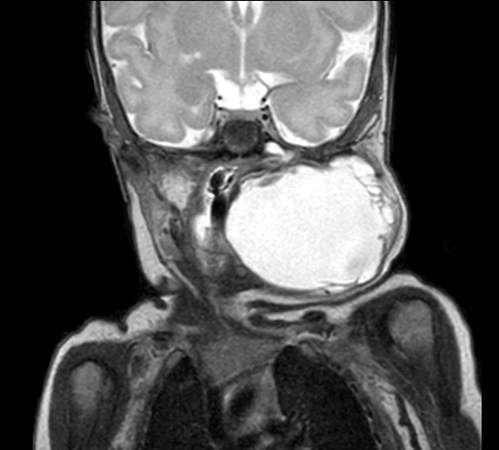

Coronal mDIXON XD - T1w TSE (Water only)

Coronal mDIXON XD - T1w TSE (In Phase)